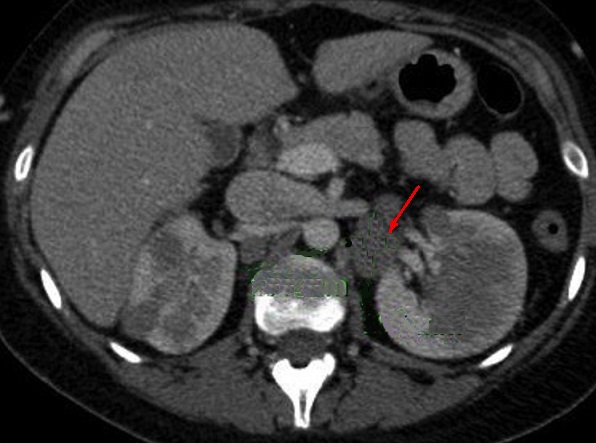

En association de lymphome de

la

queue du pancreas on peut retruuver image des

adenopathies aspect hypodense ovalaire situe sous diapragmatique (

fleche rouge ) . Image radiologique TDM en coupe

axilaire |

|

Des adenopahthies de tumeur lymphoide

peut situe sous ou perihilaire renale ( fleche

rouge ) . Une caracteristique des lymphomes

pancreatiques est l'absence de envahissement

vasculaire et l'absence de metastase hepatique |